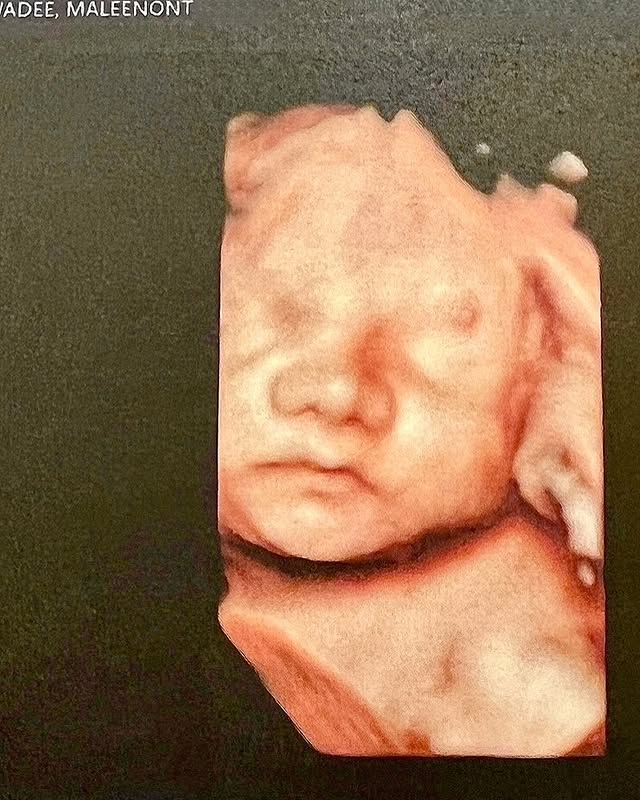

ตู่ ปิยวดี ท้อง 37 สัปดาห์ เปิดภาพอัลตร้าซาวด์ลูก คุณแม่วัย 46 บอกเริ่มหวั่นใจ

โดยล่าสุด ตู่ ปิยวดี ได้โพสต์ภาพอัลตร้าซาวด์ให้แฟนๆ ได้ดูไปด้วย ลูกน้อยในท้องต้องบอกว่าน่ารักมาก ฉายแววสวยตั้งแต่ยังไม่คลอดเลย ปากนิดจมูกหน่อย ซึ่งตอนนี้ ตู่ ปิยวดี ท้องได้ 37 สัปดาห์แล้ว และบอกว่าเริ่มหวั่นใจเบาๆ กับแคปชั่นที่แม่เขียนไว้ว่า

“หน้าเหมือนใครน๊า #เจ้าแก้มย้อย ดีผู้อุ้มท้องมา 37สัปดาห์ เริ่มหวั่นใจเบาๆ”